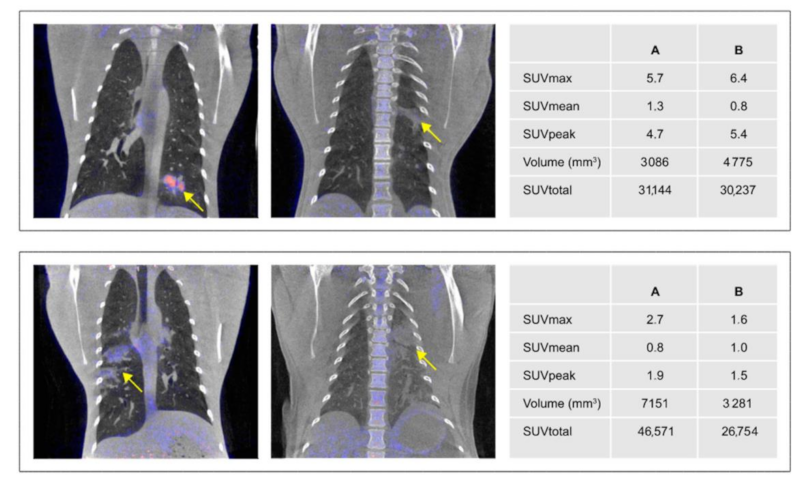

3.4.1. ROI Definition

3.4.2. Anatomical and Functional Results